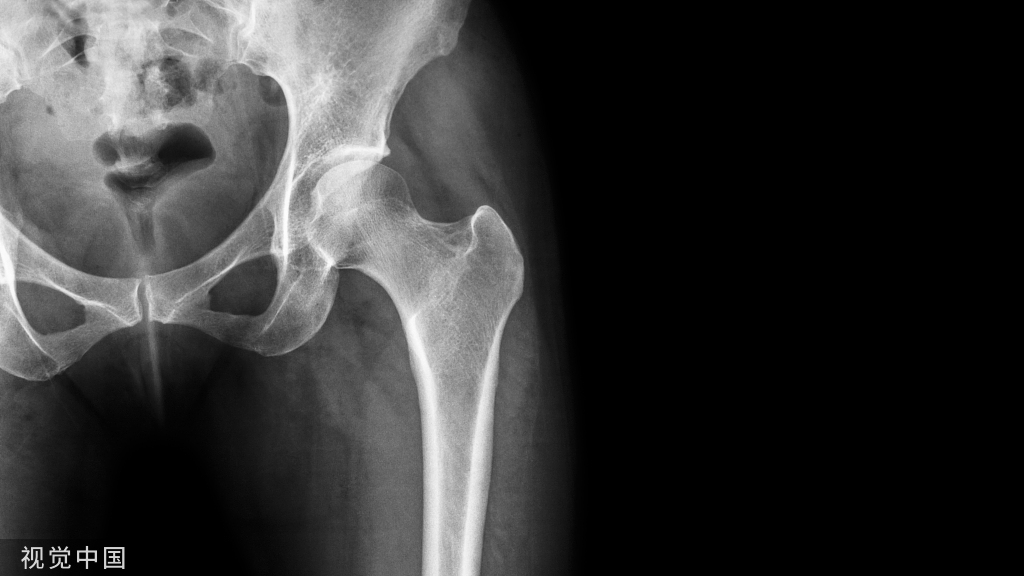

Baltalimani征阳性:脊柱严重角状后凸(SAK)的顶椎相邻椎体处于垂直翻转状态。在正位x线片上可以观察到椎体轮廓呈轴位观。

Baltalimani征阳性的正侧位X片示例。这种严重成角压迫使得脊髓损伤发生几率比阴性征象增加了61.9%